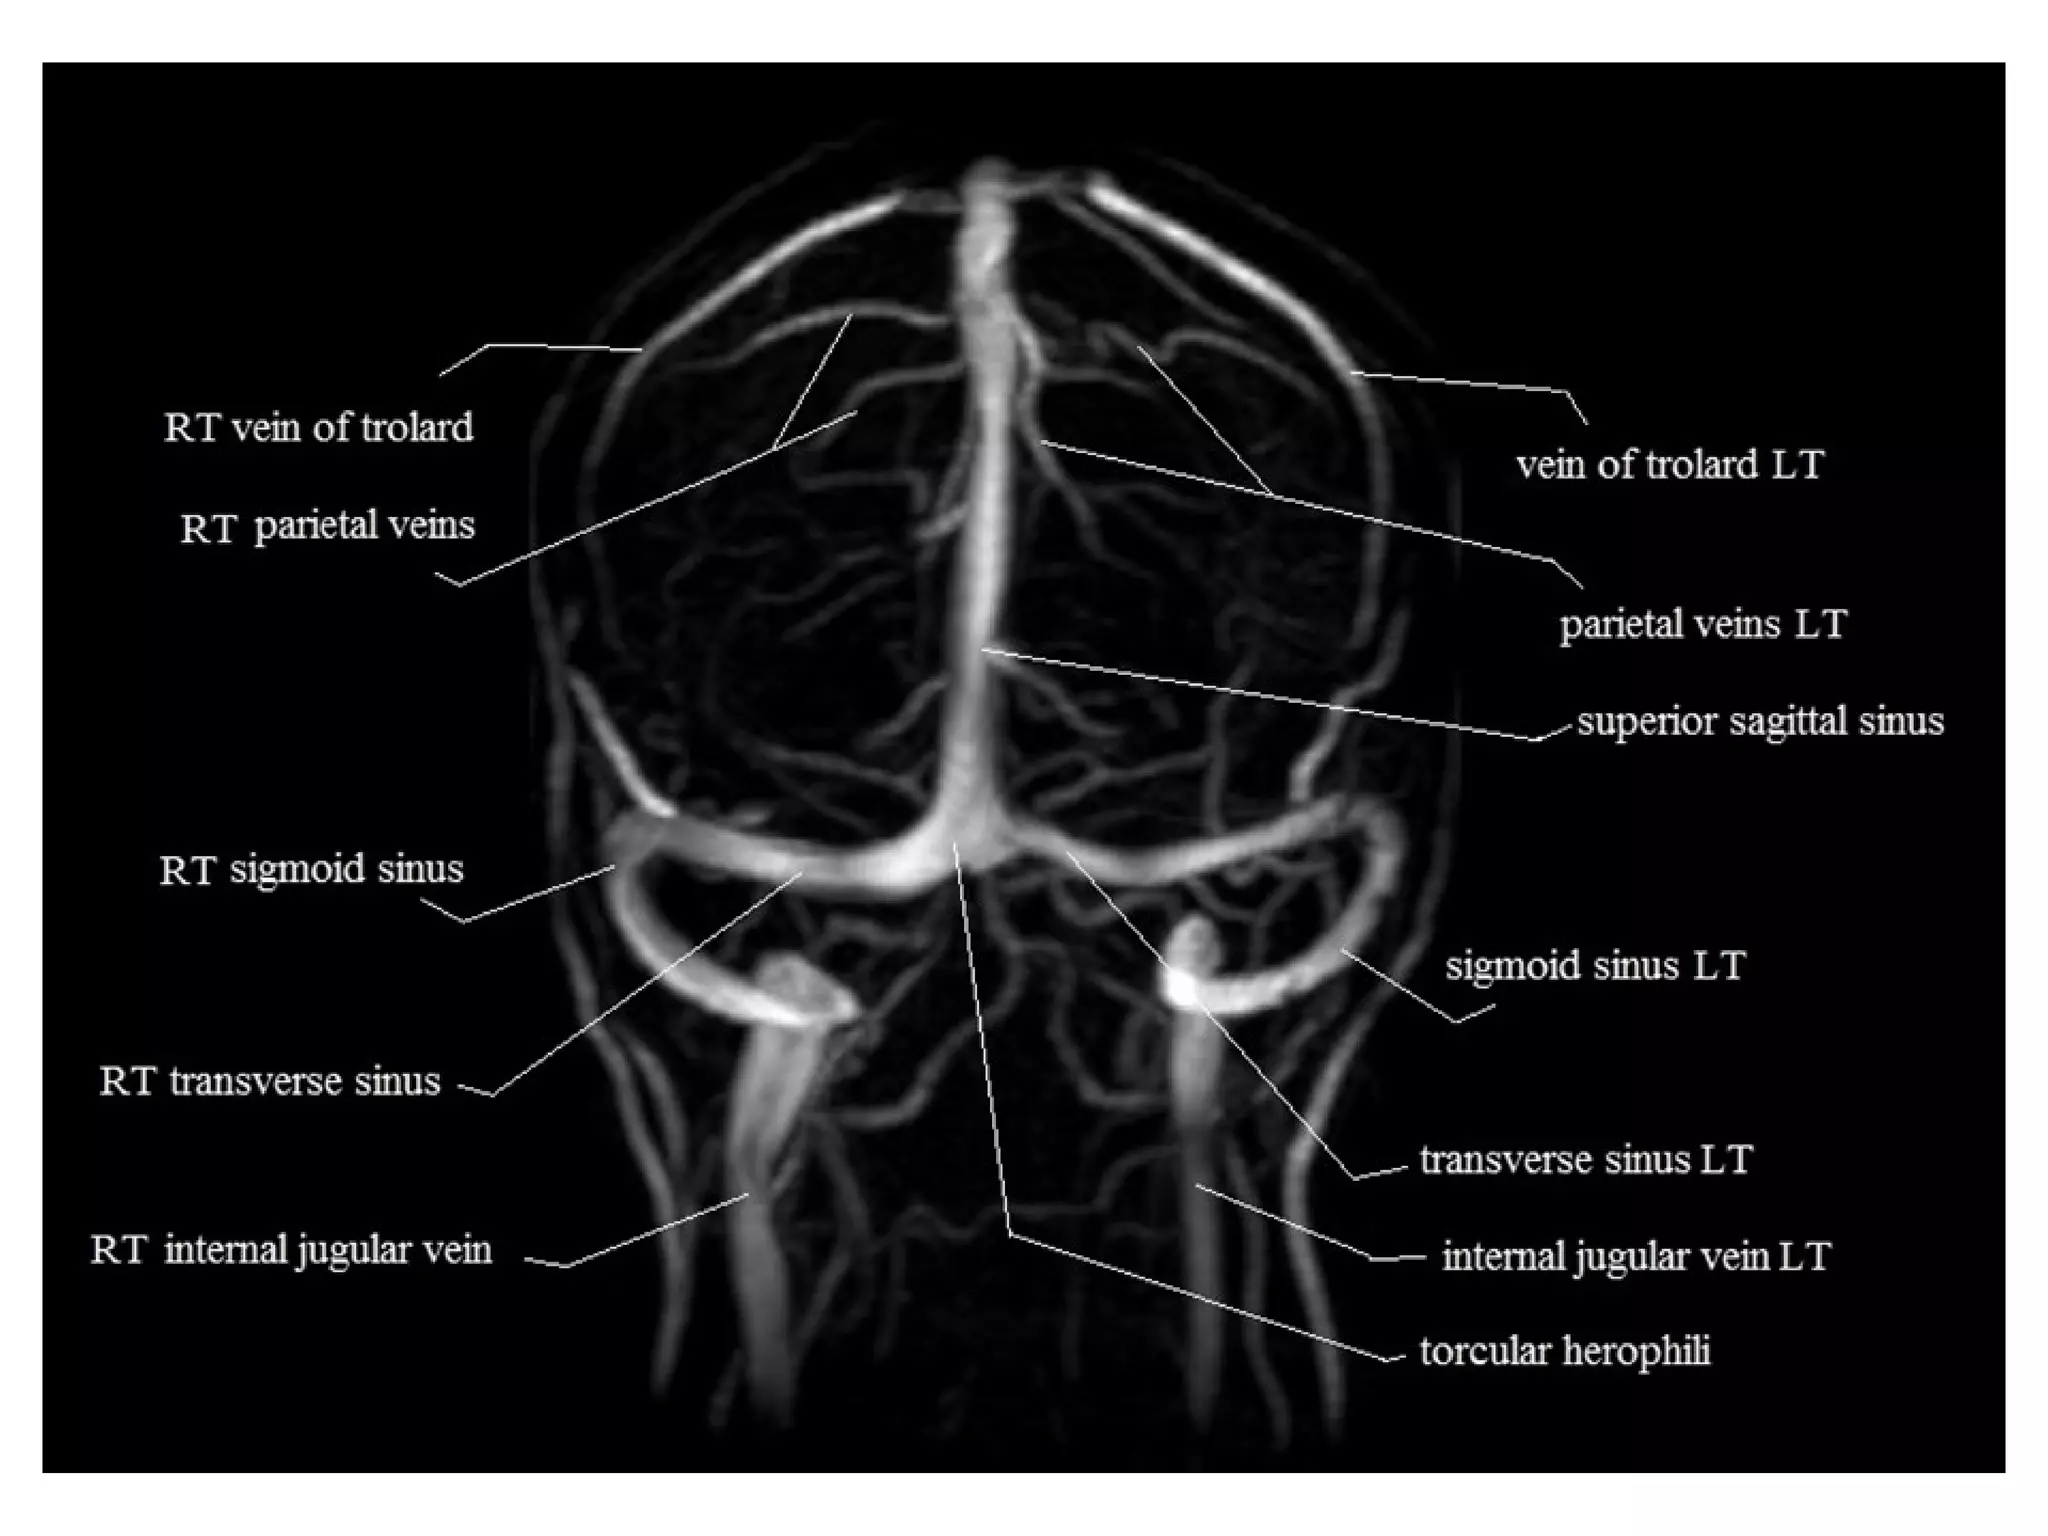

Venous Anatomy

a) Dural Sinuses

b) Deep Cerebral Veins

c) Superficial Cerebral Veins

a) Dural Sinuses :

-The superior sagittal sinus (SSS) & its tributaries

drains the motor & sensory strips

-The paired transverse sinuses are usually

asymmetric , with the left transverse sinus

often hypoplastic

-The sigmoid sinus connects to the jugular bulb

-Te torcular herophili is the confluence of the

SSS , the transverse sinus & the straight sinus

c) Superficial Cerebral Veins :

-The vein of Trolard connects superficial cortical

veins to the SSS

-The vein of Labbe drains the temporal

convexity into the transverse or sigmoid sinus